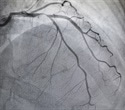

The Society for Cardiovascular Angiography and Interventions (SCAI) has released an expert consensus statement providing cardiologists, cath lab directors, and hospital leadership guidance for contemporary cath lab standards. The document, "SCAI Expert Consensus Update on Best Practices in the Cardiac Catheterization Laboratory" will be presented today at the SCAI 2021 Virtual Scientific Sessions with simultaneous publication in Catheterization & Cardiovascular Interventions. The statement has been endorsed by the American College of Cardiology Clinical Policy Approval Committee, American Heart Association, and the Heart Rhythm Society.

First released in 2012, then updated in 2016 and now 2021, the document highlights a patient- centric approach to procedures in the cardiac catheterization laboratory, incorporating all the latest advances and standards. Dividing the logistics into the pre-procedure, intra-procedure, and post-procedure periods, and including staffing, quality metrics, industry relations and governance, the document should hopefully further serve as a contemporary look at the optimal running of these busy areas. We have also included areas where operators overlap, such as interventional cardiologists and electrophysiologists, for a more collegial collaborative spirit towards these complex patients and provided guidance on procedures performed in various settings including outpatient labs."